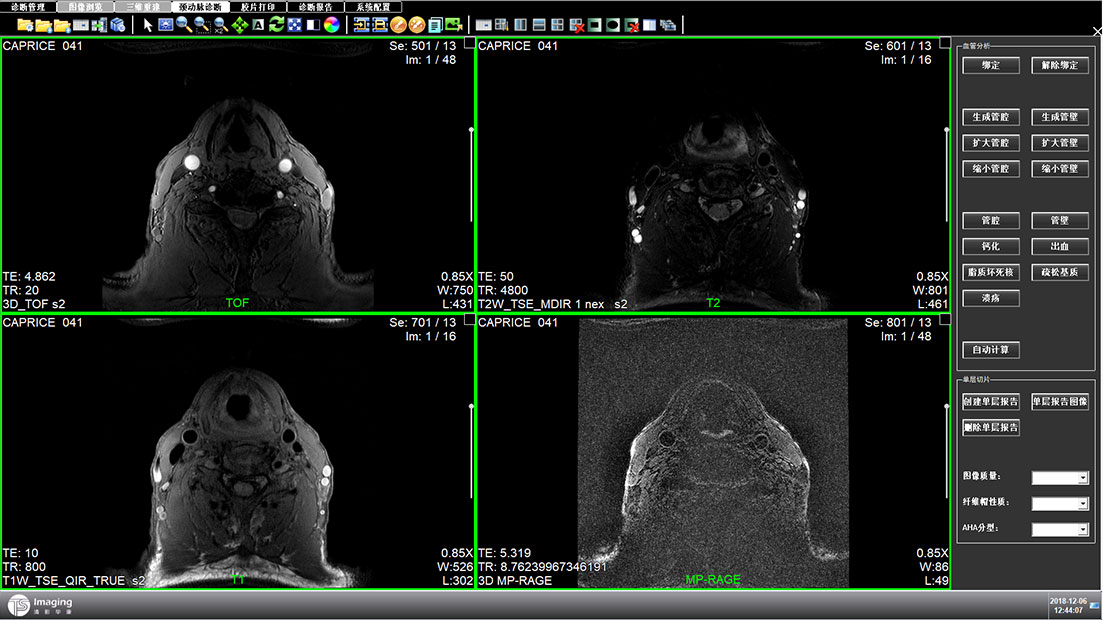

頸動脈診斷頁面

頸動脈診斷頁面整體布局和三維重建比較相似,最大的區別是右側的操作區域,血管分析都為按鍵操作,通過間隔的大小分成三部分。單層切片除了按鍵還有下拉菜單的操作。

頸動脈診斷原型